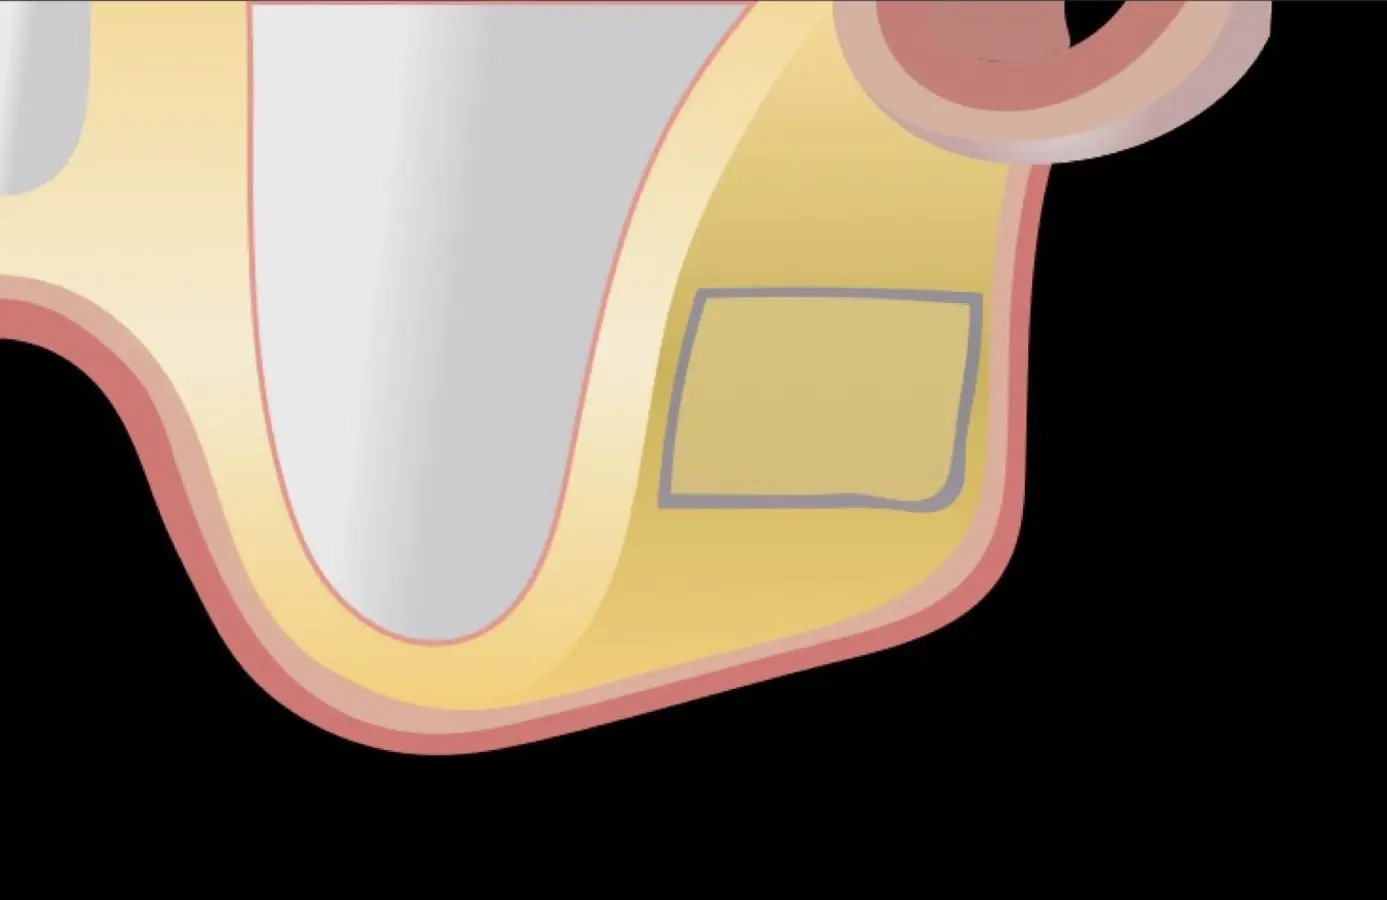

La técnica se inicia con la colocación de anestesia infiltrativa, posteriormente se realiza una incisión crestal o paracrestal con posibles liberantes verticales que deben de estar alejadas por lo menos 5 mm de los límites de la futura ventana y sobrepasar la línea mucogingival. Se realiza una elevación de colgajo, se inicia la antrostomía y antroplastía. Para ello, se emplea el inserto redondo diamantado de corte al momento de delimitar los bordes de la ventana de acceso. Luego se cambia al inserto aserrado liso de calibre fino con superficie diamantada, para profundizar y eliminar el hueso en el contorno de la ventana. Una vez que se traslucen los tejidos, se puede optar por el retiro de la tapa ósea o el levantamiento de ésta junto con la membrana.

Se inicia la elevación de la membrana de Schneider con el inserto redondeado no cortante en forma de disco, empleando movimientos suaves. El levantamiento puede complementarse con elevadores convencionales, siguiendo la dirección mesiodistal. La fase de desprendimiento inicia con el piso y sigue hacia la pared mesial para terminar, y de ser necesario, hacia la pared posterior. Existen diversos insertos con angulaciones y longitudes para mayor accesibilidad16 (Figura 1).

El clínico puede retirar la tabla ósea o introducirla como “tienda de campaña” dentro del seno maxilar. En cualquiera de las alternativas, es importante evaluar la presencia de tabiques óseos y de la arteria postero alveolar superior.